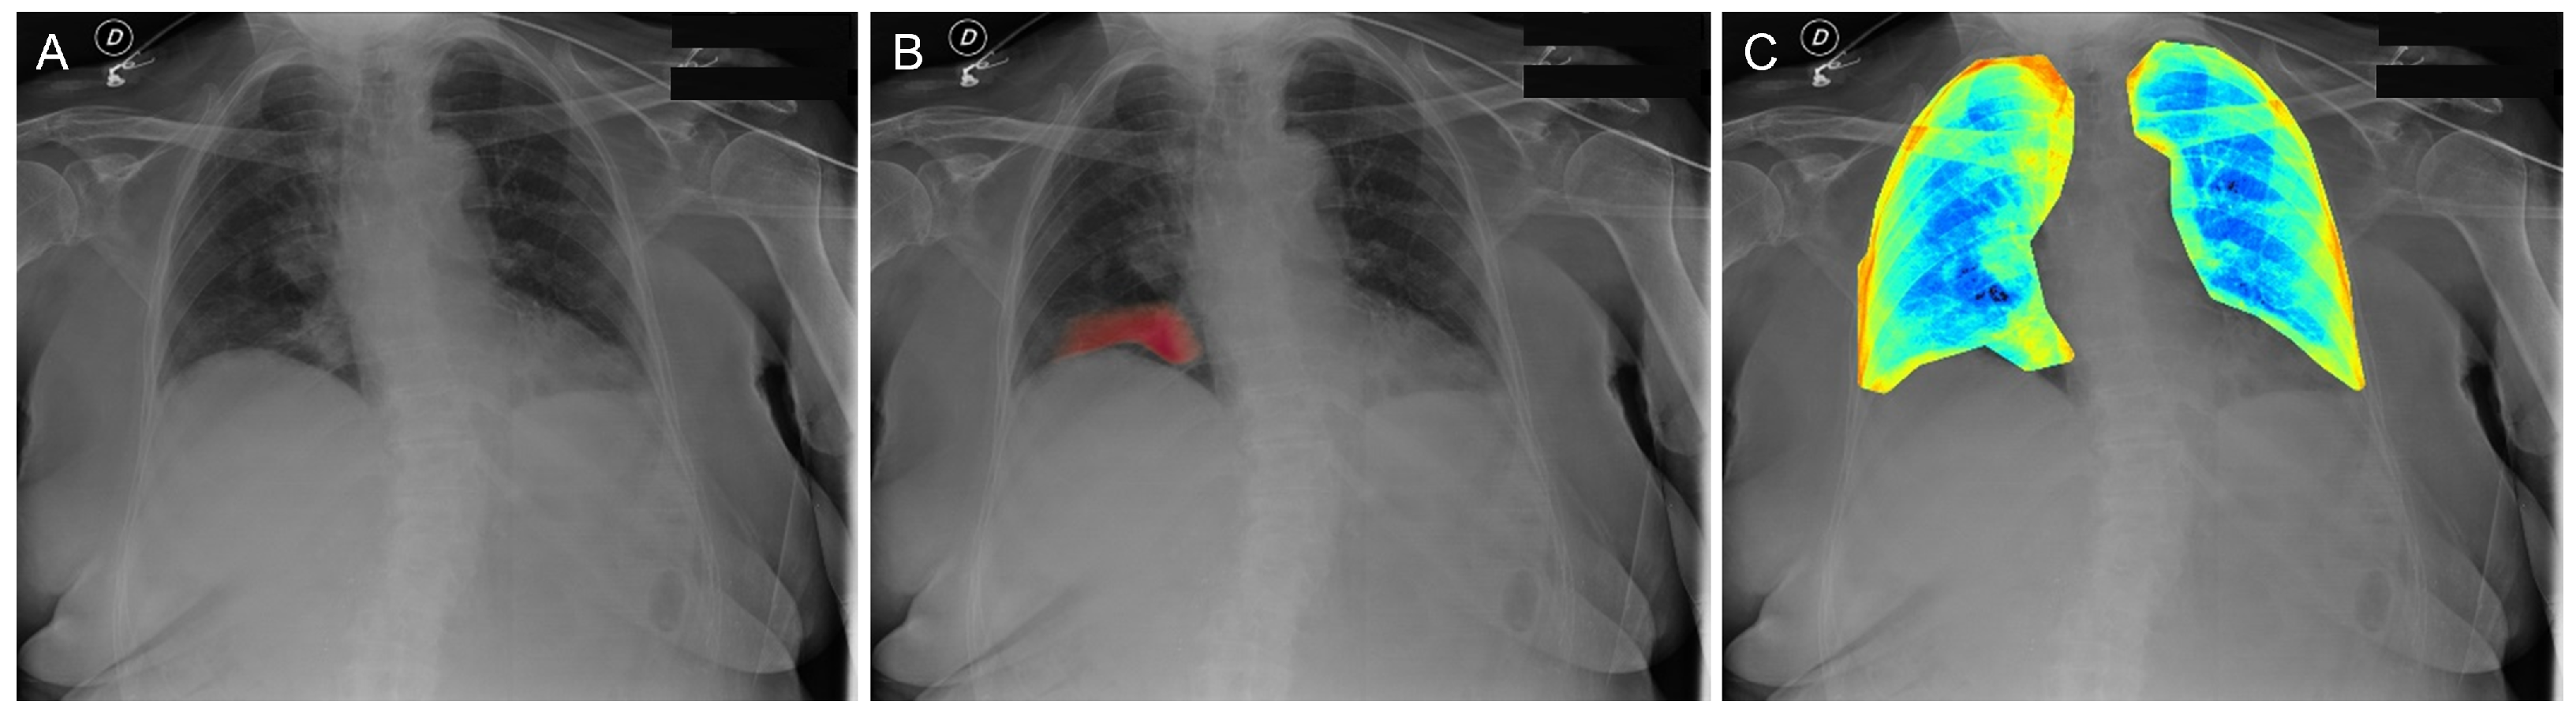

2.2. Radiomic Features Collection and Neural Network Findings